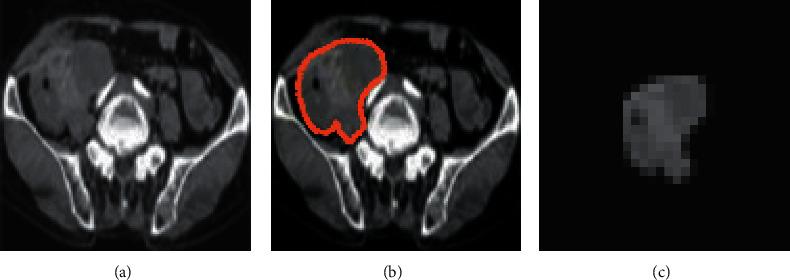

The aim of this research was to investigate the predictive role of texture features in computed tomography (CT) images based on artificial intelligence (AI) algorithms for colorectal liver metastases (CRLM). A total of 150 patients with colorectal cancer who were admitted to the hospital were selected as the research objects and randomly divided into three groups with 50 cases in each group. The patients who were found to suffer from the CRLM in the initial examination were included in group A. Patients who were found with CRLM in the follow-up were assigned to group B (B1: metastasis within 0.5 years, 16 cases; B2: metastasis within 0.5-1.0 years, 17 cases; and B3: metastasis within 1.0-2.0 years, 17 cases). Patients without liver metastases during the initial examination and subsequent follow-up were designated as group C. Image textures were analyzed for patients in each group. The prediction accuracy, sensitivity, and specificity of CRLM in patients with six classifiers were calculated, based on which the receiver operator characteristic (ROC) curves were drawn. The results showed that the logistic regression (LR) classifier had the highest prediction accuracy, sensitivity, and specificity, showing the best prediction effect, followed by the linear discriminant (LD) classifier. The prediction accuracy, sensitivity, and specificity of the LR classifier were higher in group B1 and group B3, and the prediction effect was better than that in group B2. The texture features of CT images based on the AI algorithms showed a good prediction effect on CRLM and had a guiding significance for the early diagnosis and treatment of CRLM. In addition, the LR classifier showed the best prediction effect and high clinical value and can be popularized and applied.